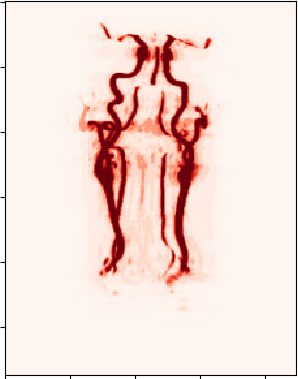

To address the drawbacks of existing approaches, we introduce a network structure which is able to generate accurate volumetric segmentation masks of very large 3D volumes. The main idea is to integrate maximum intensity projection (MIP) layers from different directions which transform the data to 2D images containing information of the full 3D image. As an example, we test the network for segmenting blood vessels (arteries and veins) in magnetic resonance angiography (MRA) scans (Figure 1.1).

We aim at generating volumetric binary segmentation masks. In particular, as one targeted application, we aim at segmenting blood vessels (arteries and veins) which assists the doctor to detect abnormalities like stenosis or aneurysms. Furthermore, the medical sector is looking for a fully automated method to evaluate large cohorts in the future. The Department of Neuroradiology Innsbruck has provided volumetric MRA scans of 119 different patients. The images face the arteries and veins between the brain and the chest. Fortunately, also the volumetric segmentation masks (ground truths) of these 119 patients have been provided. These segmentation masks have been generated by hand which is long hard work (Figure 1.1).

We first solve a 2D version of our problem. This can be done by applying maximum intensity projections to the 3D data and the corresponding 3D ground truths. Using a rotation angle of around the vertical axis we obtain 10 MIP images out of each patient, which results in a data set to 1190 pairs of 2D images and corresponding 2D segmentation masks. Data corresponding for one patient are shown in Figure 2.1.